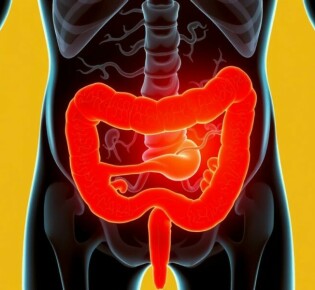

La flora bacteriana implicada en la apendicitis: un mundo microscópico que enciende un órgano olvidado